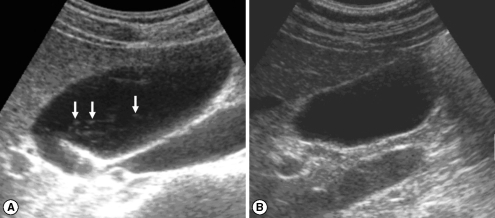

In the initial (pre-treatment) sonography of the 83 cured patients after treatment, DDIHD, IPDE, and FEFGB were found in 82 (98.2%), 42 (50.6%), and 32 (38.6%), respectively (Table 3). After treatment, DDIHD, IPDE, and FEFGB were found in 80 (96.4%), 45 (54.2%), and 17 (20.5%), respectively. DDIHD was improved in 3 (Fig. 1), aggravated in 1, and unchanged in 79 patients. IPDE was improved in 5 (Fig. 2), aggravated in 8, and unchanged in 70 patients. FEFGB was improved in 20 (Fig. 3), aggravated in 5, and unchanged in 58 patients. Neither DDIHD nor IPDE showed significant changes (P = 0.625 and P = 0.581, respectively). However, FEFGB revealed a statistically significant improvement (P = 0.004) (Table 3).